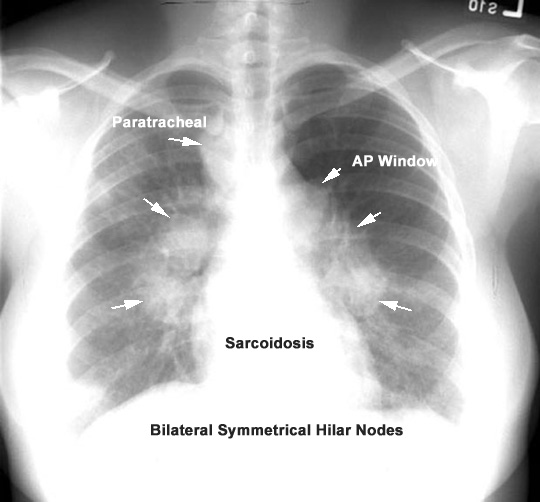

The significance of the problem in adults is not minimal. Surrounding granulation tissue and secretions can obscure the margins making it difficult to correctly identify the nature of the obstructing lesion.įoreign body aspiration is detailed extensively in children but less frequently in adults. Clinically, aspirated foreign bodies may commonly be confused with endobronchial malignancies based on the similar radiographic findings and initial gross appearances. Foreign body identified as popcorn kernel.Ĭ. Using cryotherapy, the foreign body was successfully removed and eventually identified as a popcorn kernel ( Figure 5).įigure 5. Repeat bronchoscopy was performed with results as shown in Video 1.īronchoscopy revealed a foreign body in the left upper lobe bronchus. The patient was transferred on mechanical ventilation to a tertiary care center for further evaluation of suspected endobronchial malignancy. She was electively intubated for the procedure and bronchoscopy revealed an endobronchial lesion in the LUL. The patient was admitted to the outside hospital and underwent bronchoscopy for evaluation of left upper lobe (LUL) and lingular collapse. Computed tomography image of the chest demonstrating left upper lobe (LUL) consolidation with endobronchial lesion in LUL bronchus. Computed tomography image of the chest demonstrating consolidation of the left upper lobe.įigure 4. Two cuts are provided below ( Figures 3 and 4).įigure 3. Subsequently the patient underwent computed tomography (CT) of the chest with pulmonary angiography. Lateral view on chest x-ray demonstrating left upper lobe consolidation. Posterior-anterior chest x-ray demonstrating left sided consolidation without volume loss.įigure 2. Posterior-anterior (PA) and lateral films were provided ( Figures 1 and 2).įigure 1. She presented to an outside hospital emergency department and was found to have an abnormal chest x-ray.